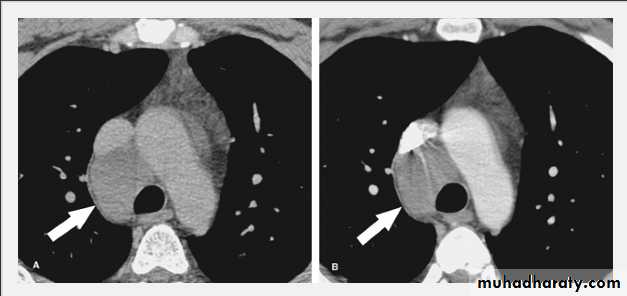

Bronchogenic Cyst. Unenhanced (A) and enhanced (B) CT scans in a 38-year-old man demonstrate a smooth, low-attenuation paratracheal mass (arrows) that fails to enhance, consistent with a bronchogenic cyst.